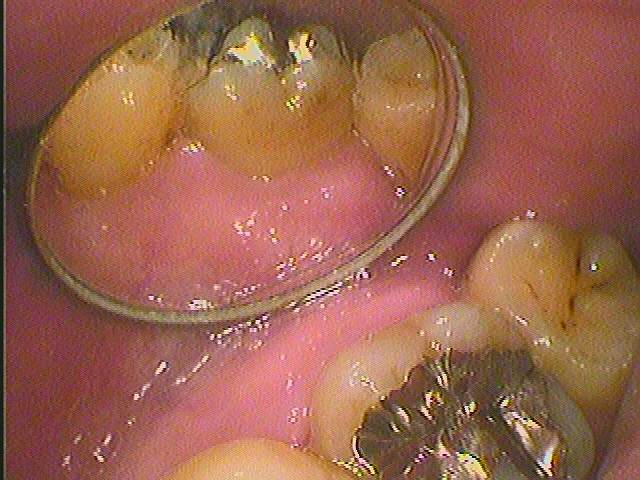

この7番の銀歯がはいいている歯が原因なのですが、、、

外見からは分かりにくいです

この銀歯が確かに原因だとわかりましたのでこの銀歯を外していきます

銀歯を外していくとこのようになっています

遠心部に虫歯があり神経もCT精査通り失活していました